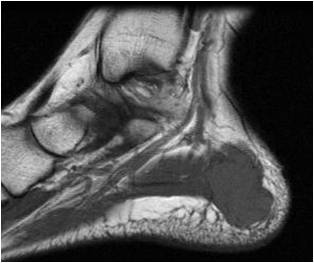

Fig. 1 & 2: MRI Sagittal (Fig. 1) and Coronal (Fig. 2) T1 images of the right foot demonstrating a well-circumscribed soft tissue mass with mildly increased signal compared with muscle, located along the medial aspect of the calcaneous bone. No marrow abnormalities or surrounding soft tissue edema is noted.